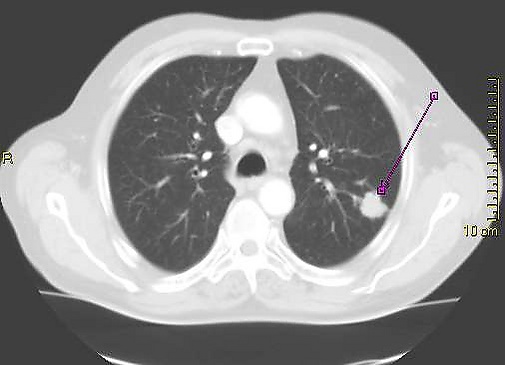

Солитарный лёгочный узел (одиночное периферическое образование) — в рентгенологии, периферическое образование в лёгочной ткани размером менее 3 см. Может быть случайной находкой на 0,2 % рентгенограмм грудной клетки[1] и около 1 % компьютерных томограмм[2].

Солитарные лёгочные узлы следует отличать от инфильтратов, более крупных опухолей или образований с иными сопутствующими радиологическими симптомами. Солитарный лёгочный узел представляет собой единичный периферический очаг, со всех сторон окружённый лёгочной тканью, диаметром менее 3 см, не ассоциированный с пневмонией, ателектазом или лимфаденопатией[3][4].

Дифференцировать злокачественное периферическое образование от доброкачественного помогают некоторые особенности. Учитывается размер образования: чем оно меньше, тем меньше риск злокачественности. Доброкачественные образования обычно имеют чёткие контуры, злокачественные имеют неравномерные, местами нечёткие границы или дольчатую структуру[4]. При наличии в образовании полости имеет значение толщина её стенок: чем тоньше стенка, тем более вероятна его доброкачественная природа и наоборот (наиболее достоверна толщина стенок менее 4 мм или более 16 мм, соответственно)[4]. При раке лёгкого полость в толще очага обусловлена некрозом (распадом) или вторичным абсцедированием. Если на фоне очага визуализируются воздушные полоски бронхов (воздушная бронхограмма), следует заподозрить бронхиолоальвеолярный рак.